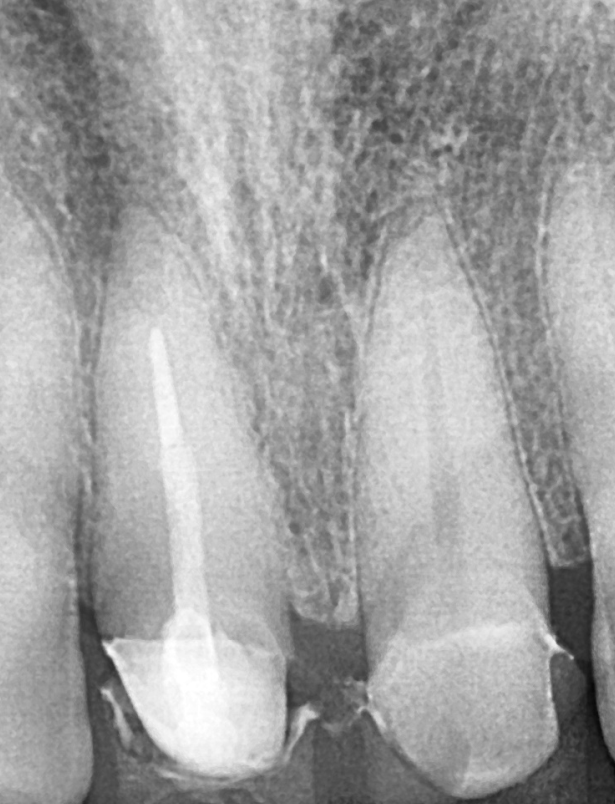

조심스럽게 신경치료를 하는 순간,

예상했던 일이 벌어졌습니다.

250630

신경관 입구에 접근하자마자

금 간 부위를 중심으로 치아가 깨져나간 겁니다.

역시나 남은 치아량이 매우 적어,

신경치료를 마친 후 포스트(기둥)으로 보강해야 했습니다.

250630 앞니 금 갔을 때, 방치하면 안 되는 진짜 이유 <파절 치료 사례>

그래야 나중에 씌울 크라운의 유지력을 확보할 수 있기 때문입니다.

왼쪽 앞니는 금은 있었지만 파절이 심하지 않았고,

통증도 없어서 신경치료 없이 크라운만

씌우기로 결정했습니다.